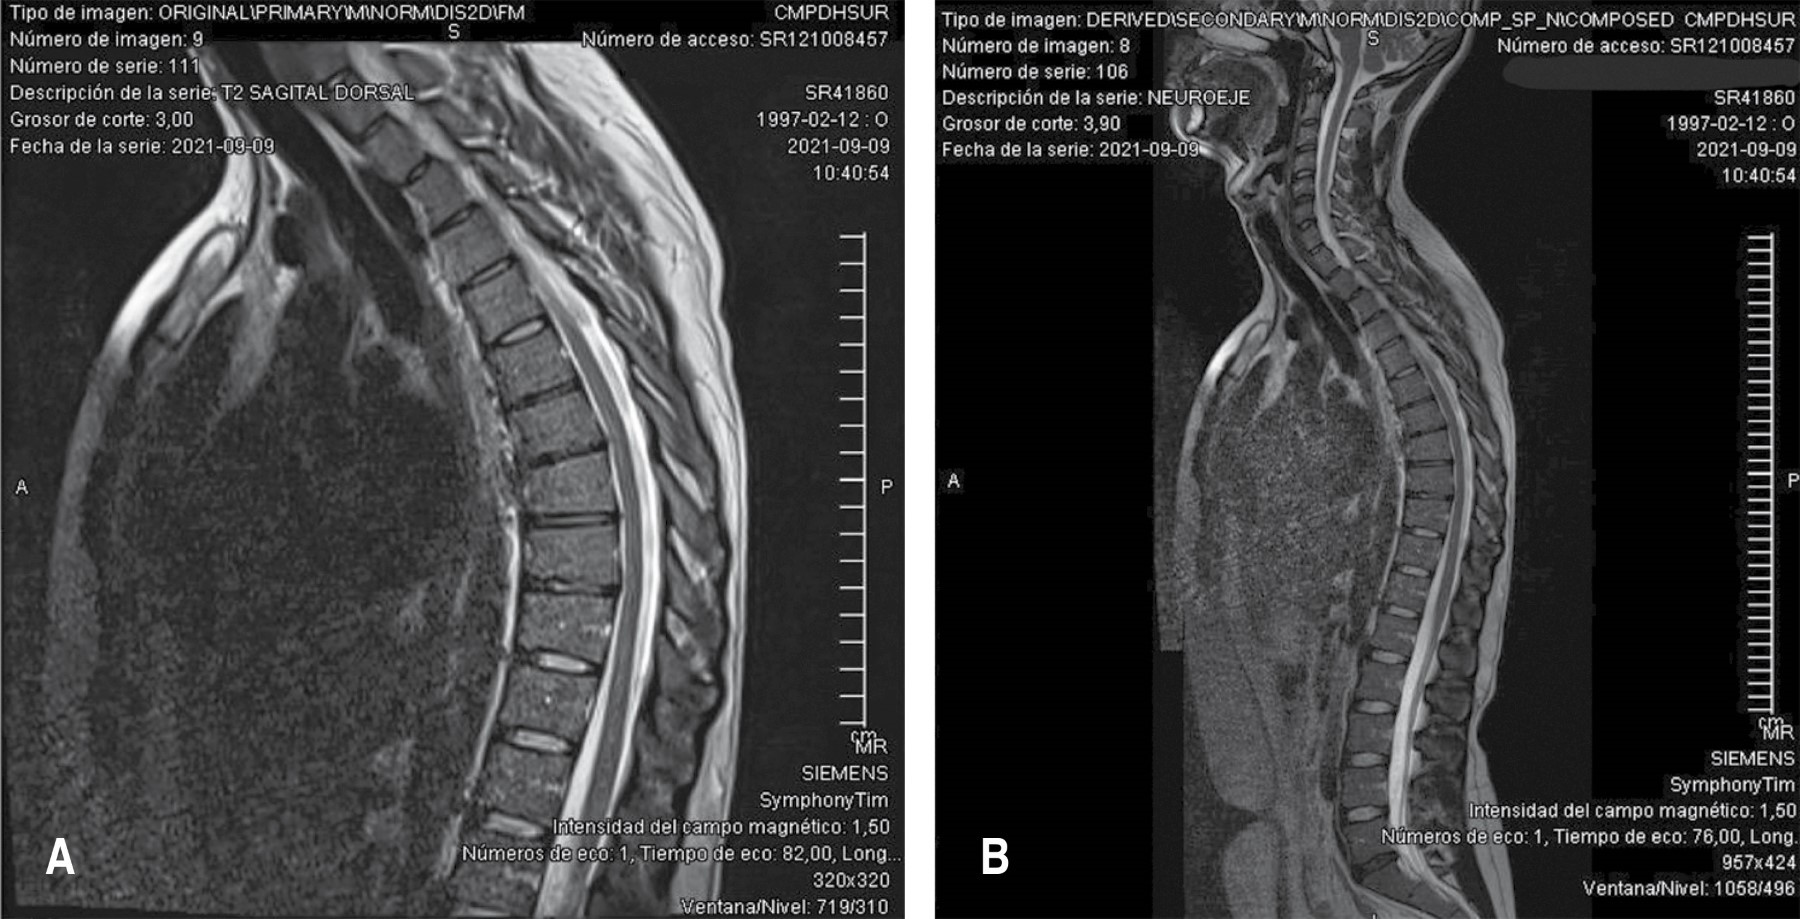

Caso 1. Paciente masculino de 12 años con estatura de 1.65 m y peso de 43 kg (índice de masa corporal [IMC] 15.79, bajo peso). Acude por dolor en columna dorsolumbar de 4-5 años de evolución, que se exacerba al estar acostado y al cargar objetos pesados. Presenta hipercifosis, con prueba de Adams negativa. Deambulación adecuada con capacidad de realizar prueba punta-talón. La exploración de miotomas y dermatomas se encuentra sin alteraciones, sin datos de neurotensión ni sacroilitis. No presenta datos de radiculopatía ni señales de alarma. Los estudios de resonancia magnética nuclear (RMN) y radiografías confirman el diagnóstico de enfermedad de Scheuermann, evidenciando afectación de 4-5 vértebras y una cifosis dorsal de 60 grados. Se indica tratamiento con corsé y seguimiento en seis meses con radiografía de control (Tablas 1 y 2; Figura 1).

Caso 4. Paciente masculino de 24 años con estatura de 1.83 m y peso de 83 kg (IMC 24.78, peso normal). Presenta dolor irradiado a miembro pélvico derecho y miembro torácico derecho. Deambulación normal con capacidad de realizar prueba punta-talón. Presenta hiperelasticidad y reflejos osteotendinosos hiperrefléxicos. Refiere parestesias en región glútea, lateral de muslo y pierna derechos. La RM muestra deshidratación discal dorsal con acuñamiento vertebral de T6 a T9. Se indican recomendaciones generales y se instruye continuar con actividad física para fortalecimiento muscular con cita anual (Tablas 1 y 2; Figuras 2 y 3).

La deformidad cifótica es un hallazgo constante, pero con variaciones en su severidad, y frecuentemente se acompaña de escoliosis de grado variable. Se encontró una variabilidad significativa tanto en el plano sagital como coronal. En el plano sagital, la cifosis dorsal oscila entre 50° y 70°, presentándose los casos más severos en un adolescente de 16 años (70°) y en un adulto de 33 años (65°), mientras que los casos más leves se observaron en individuos más jóvenes. En el plano coronal, los pacientes presentan deformidades escolióticas con un espectro desde curvas leves (< 10°) hasta moderadas (30° torácica izquierda), con algunos casos que presentaron patrones de doble curva. Además, los cambios estructurales incluyen con frecuencia acuñamiento vertebral de 4-5 vértebras, con cambios discales más prominentes en adultos.